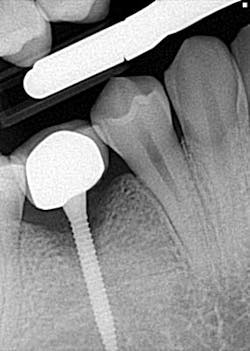

Hygiene. It can be agreed upon that if an implant can’t be kept clean, then the potential for failure and difficulties rise exponentially. A 90-degree angle between the implant and crown is virtually impossible to keep clean and maintain. As amazing as some hygienists are, it is impractical to expect that a curette can get into that space to clean it without making hamburger of the tissue. The implants were cemented on, so they are not easily retrievable. The emergence profile is nonexistent. Do natural teeth look like this? I would submit that when restoring implants, it is our job to mimic the shape and emergence profile of natural teeth as closely as possible. When we don’t, then we lose the inherent cooperation and benefits that the tissue can provide. To help the parents understand this concern, I showed them an example of a traditional implant vs. the “pumpkin on a toothpick” implant. The side-by-side comparison spoke for itself.

vs.